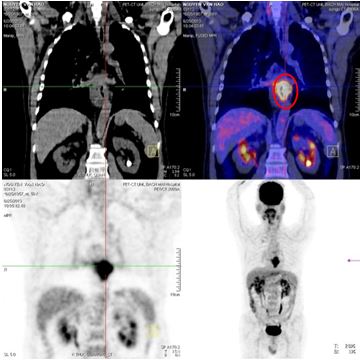

- Bệnh nhân được chụp PET/CT để đánh giá sau điều trị

- Chụp PET/CT:

Hình 7: Hình ảnh chụp PET/CT:

- Tăng hấp thu FDG tại vùng xoang lê phải (theo dõi viêm)

- Không thấy tăng hấp thu FDG bất thường tại các vị trí khác trong cơ thể

So sánh trước và sau điều trị:

| Trước điều trị: U xoang lê phải, kích thước: 1,5x 2x2,5 cm, max SUV 9,47 | Sau điều trị: không thấy u, theo dõi tổn thương viêm do xạ trị |

Trước điều trị: u thực quản, kích thước: 3x4,6x6,7 cm, maxSUV 10,72 Sau điều trị: không thấy u